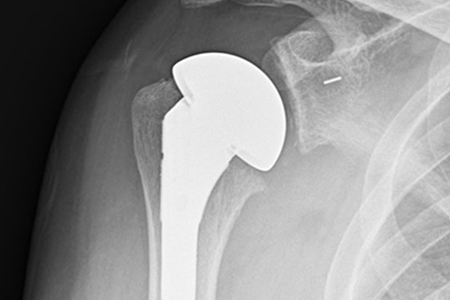

수술 치료

초기에는 약물치료를 할 수 있으나 고령이면서 통증이 잘 조절되지 않고 가성마비가 생긴 경우 인공관절 치환술을 통해 회복할 수 있습니다.

어깨부위 방사선(X-ray) 검사를 통해 관절염 여부를 확인할 수

있습니다. 검사상 어깨 뼈 사이가 좁아지거나 비정상적인 골극이

생성되어 관절면이 불규칙적이며 굳어있는 것이 관찰됩니다.

CT와 MRI 정밀검사를 통해 어깨 관절 변형 정도를 정확하게

파악해 볼 수도 있습니다.